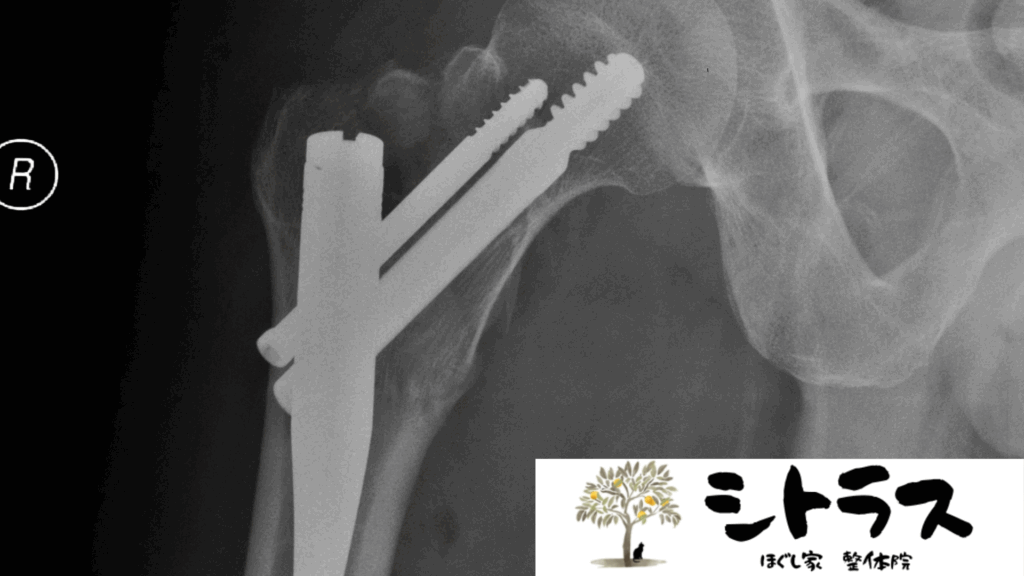

大腿骨頸部骨折は高齢者に多い代表的な骨折で、転倒や骨粗鬆症によって発生します。骨折後は多くの場合、人工骨頭置換術や骨接合術などの手術が行われます。しかし、手術によって骨が固定されても、その後のリハビリや生活環境整備が十分でないと 後遺症 が残ることがあります。

4. 下肢の長さの不一致(脚長差)

人工骨頭置換術後に脚の長さが微妙に変わることがあります。脚長差は骨盤や腰椎に影響を与え、腰痛や姿勢不良を招きやすくなります。